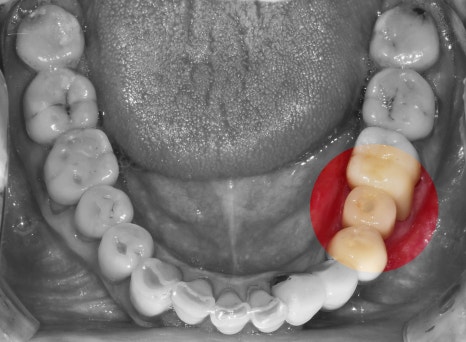

뼈와 다 아물게 되면, 오른쪽 사진에서

보실 수 있는 것 처럼 지르코니아 크라운이

연결이 되면 모든 시술은 끝나게 됩니다.

하악에만 지르코니아 크라운이 연결되었습니다.